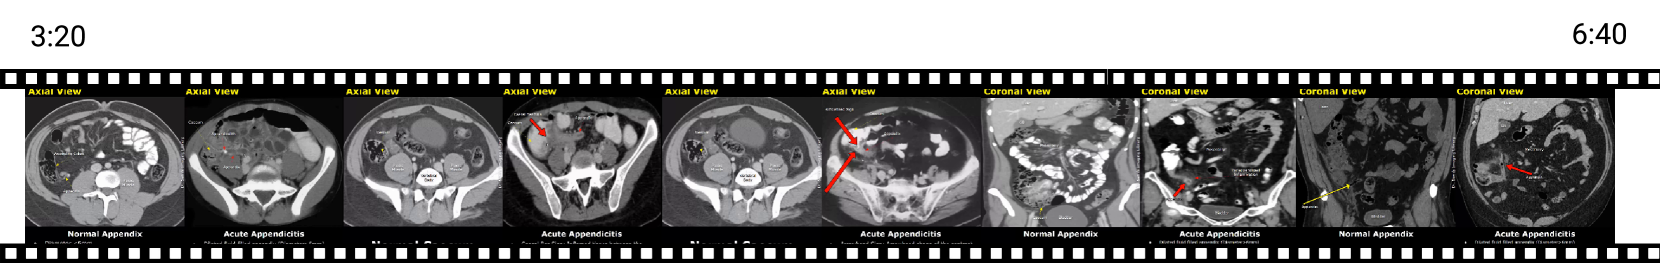

SurgeryVideoQA.

This benchmark evaluates VLMs in the domain of open surgery. From the cleaned fine-tuning dataset, a human expert manually inspected all videos to select those that were relatively clean, excluding content with overlaid text or answers and ensuring that the majority of each video contained relevant biomedical content. Through this process, we identified 471 high-quality surgical procedure videos, totaling 21.9 hours of footage.

Using the cleaned captions associated with these videos, we generated multi-turn Q/A pairs with GPT-4o (prompt in Section C.5). We optimized prompt for generating questions that assess a model’s understanding of procedural steps, anatomical structures, surgical tools, and intraoperative decision-making. The Q/A format consists of concise, open-ended answers rather than multiple-choice options, providing a more challenging and realistic setting for biomedical applications. A medical doctor then manually reviewed all videos and their corresponding Q/A pairs to remove any trivial or non-relevant questions.

Figure 6 presents the distribution of the SurgeryVideoQA dataset. The dataset contains 2,692 Q/A pairs, with an average of 5.7 pairs per video. The predominant anatomical regions are the gastrointestinal system (5.9 hours, 141 videos), head and neck (5.2 hours, 100 videos), and the skin and integumentary system (3.8 hours, 79 videos). Qualitative examples of the SurgeryVideoQA dataset are provided in Section D.2. The distribution of video resolutions in the SurgeryVideoQA dataset is shown in Appendix Figure 8.